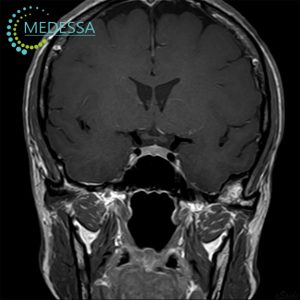

МРТ – найефективніший метод дослідження стану мозку. Він не лише безпечний і неінвазивний, а й надає детальну та точну інформацію, без впливу шкідливого опромінення, на відміну від рентгену чи КТ. МРТ голови дозволяє оцінити всі структури мозку, включаючи судини, мозкові оболонки та нервові корінці.

Цей метод дозволяє своєчасно виявляти різні захворювання, такі як пухлини, метастази, запальні процеси, дегенеративні зміни, деформації та інші патології, що дає змогу лікарям поставити точний діагноз і призначити ефективне лікування.

Для виявлення навіть незначних змін застосовуються 3D-послідовності та зрізи з високою роздільною здатністю.

Як результат, лікар отримує максимально точну інформацію про патології на ранніх стадіях, включаючи пухлини, за короткий час. Загальний час сканування голови без контрасту займає близько 10-15 хвилин.